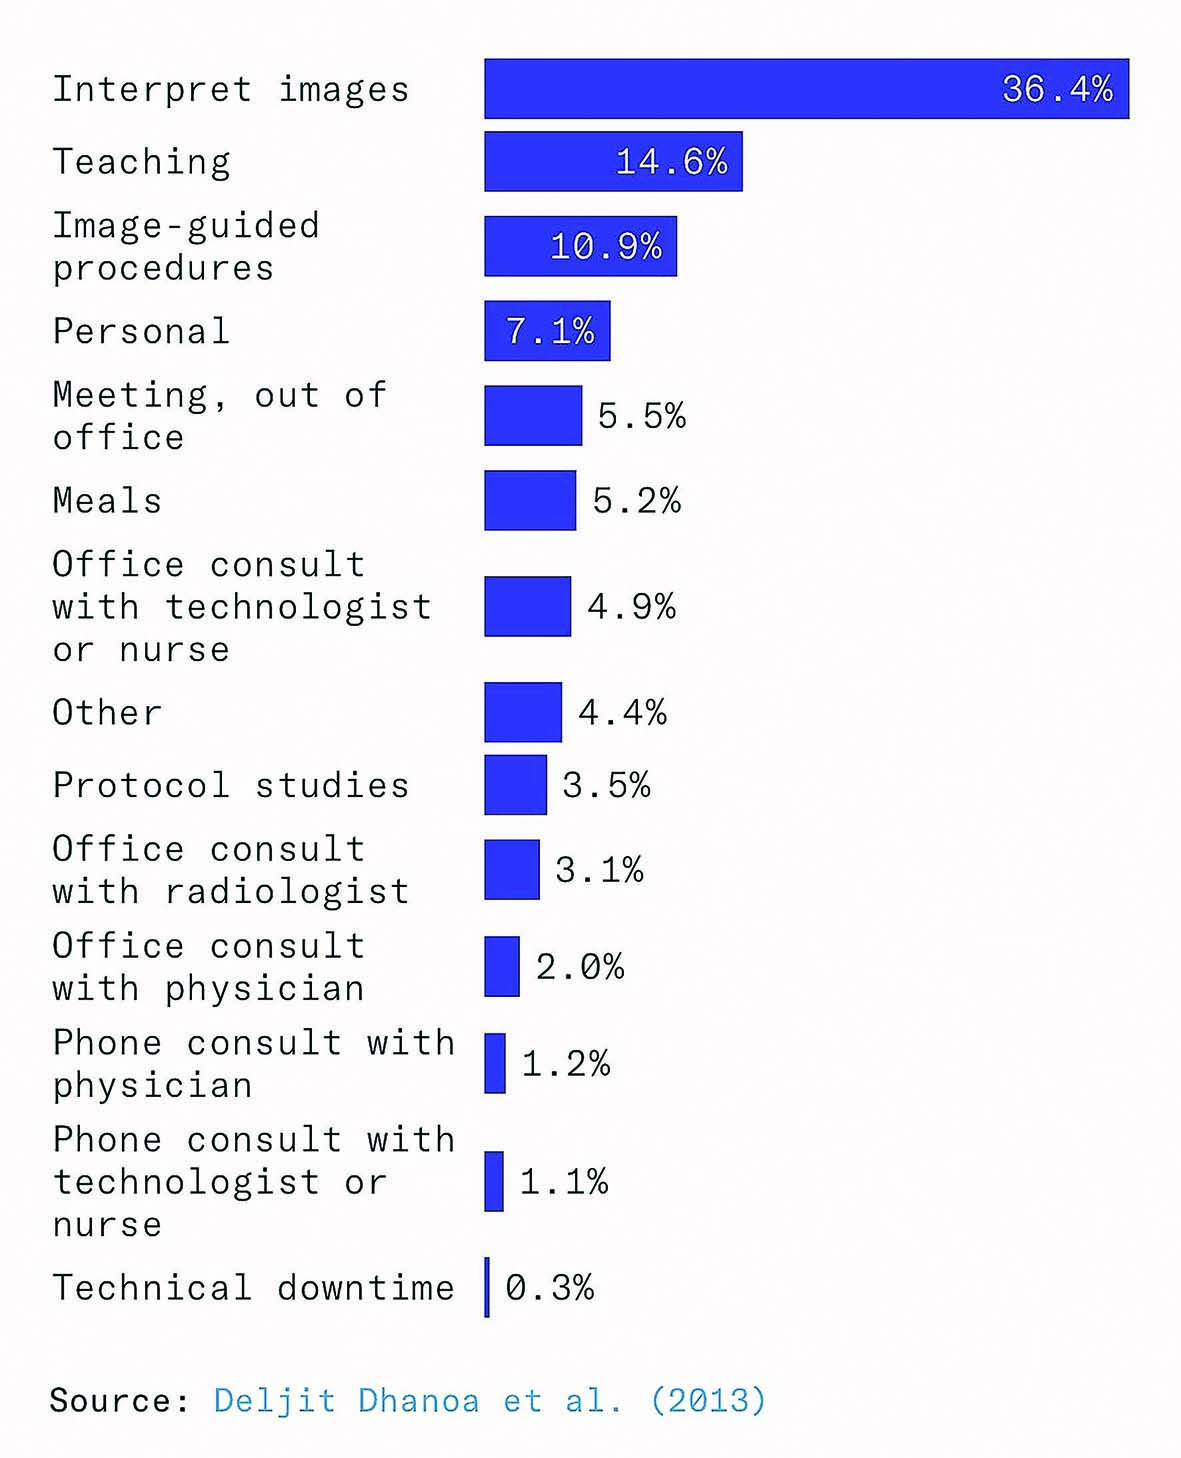

سوم، حتی زمانی که مدلها تشخیص دقیقی میدهند، فقط بخش کوچکی از وظایف یک رادیولوژیست را انجام میدهند. رادیولوژیستها تنها بخشی از زمان خود را صرف تشخیص میکنند و بخش عمده کارشان شامل گفتوگو با بیماران و دیگر پزشکان است.

حتی اگر مدلهای هوش مصنوعی آنقدر دقیق شوند که اسکنها را بهتنهایی بخوانند، رادیولوژیستها ممکن است پرمشغلهتر از قبل شوند، نه بیکار. یک مطالعه در ۲۰۱۲ نشان داد که فقط ۳۶درصد از زمان رادیولوژیستها صرف تفسیر مستقیم تصاویر میشود. بخش عمده زمان صرف مواردی چون نظارت بر تصویربرداری، ارتباط با پزشکان و بیماران، آموزش دستیاران رادیولوژی و تکنولوژیستها و بازبینی درخواستها و پروتکلهای تصویربرداری میشود. بنابراین اگر هوش مصنوعی در تفسیر تصاویر بهتر شود، رادیولوژیستها زمان خود را به سمت وظایف دیگر جابهجا میکنند و اثر جایگزینی کاهش مییابد.